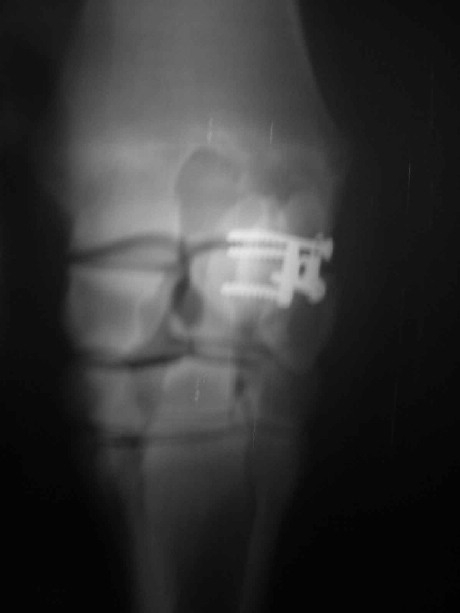

Griffelbeinfraktur

Entfernung der Splitter und Stabilisierung des Gelenksbeteiligten

Teiles mit Zugschraube